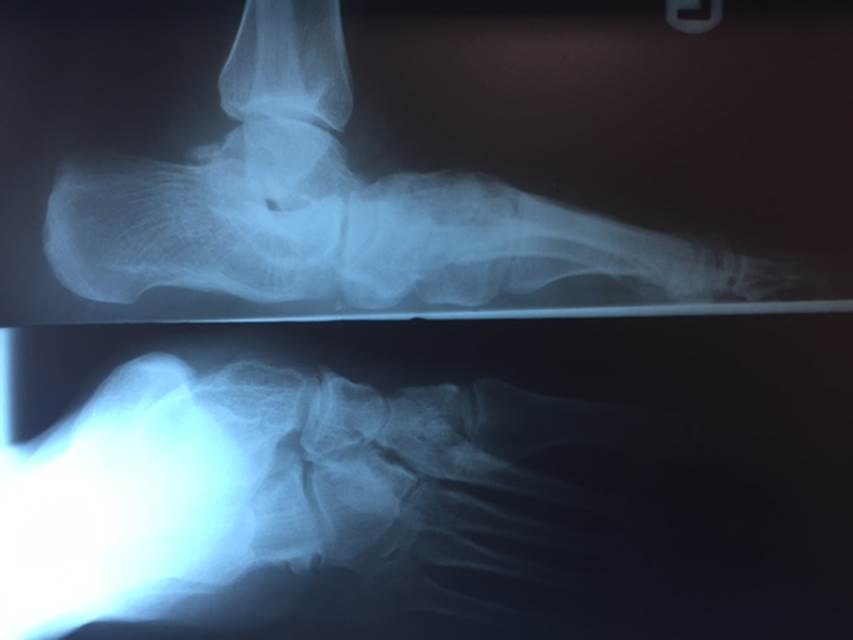

"Surgical misadventure" by another surgeon about 8 years ago. The wrong fixation was used for a flatfoot repair, & the deformity was not corrected. Patient came in with severe foot & ankle pain, with no arch at all. She was unable to play with her grandchild because the pain was so bad, & because she felt unsteady. The old hardware was removed, a lateral calcaneal lengthening osteotomy was performed along with a medial column/1st ray realignment. The ankle was painfully arthritic, & patient elected a total ankle replacement vs. an ankle fusion. She is now able to walk pain free & play with her grandchildren!